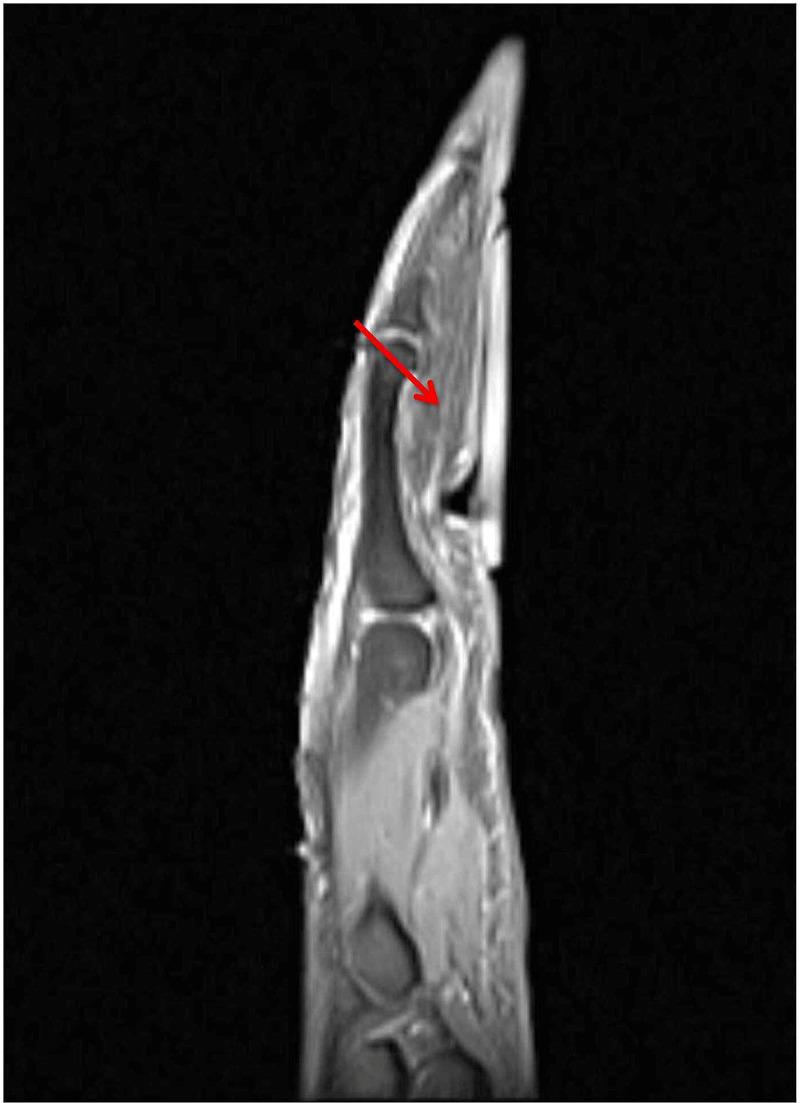

Intraneural lipomas are rare soft-tissue tumors that can occur particularly within the median nerve. Even fewer cases have been reported of their occurrence within the ulnar nerve. These masses can cause compression neuropathies. In this report, we present the first documented case of an intraneural lipoma of an ulnar digital nerve.

神经内脂肪瘤是一种罕见的软组织肿瘤,尤其可发生于正中神经内。而发生于尺神经内的病例报道则更少。这些肿物可导致压迫性神经病变。在本报告中,我们呈现了首例有记录的尺侧指神经神经内脂肪瘤病例。